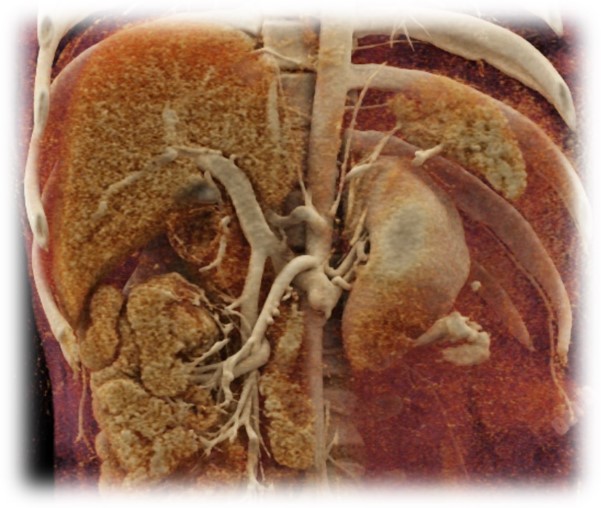

Pár kép az oktatás radiológiai részéről:

(SE-OKK, SIEMENS, CTISUS)